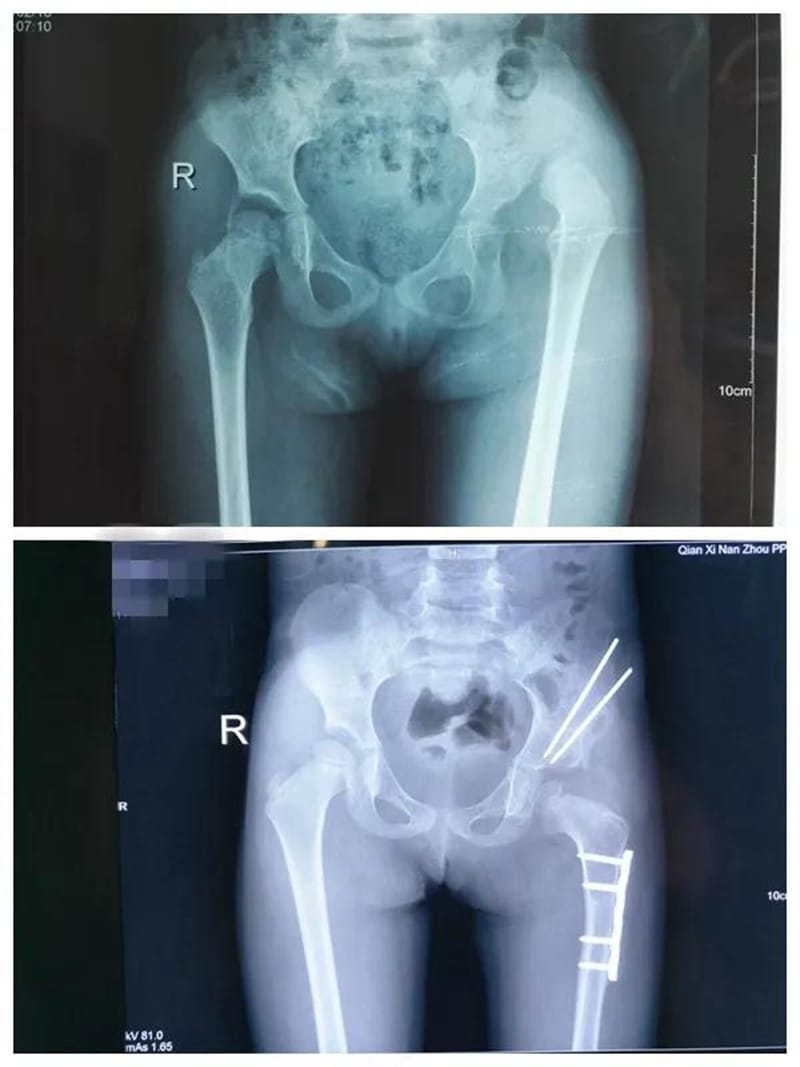

一位十七岁花季少女,因为足踝畸形长期卧床,患者曾先后到广州、昆明、贵阳等地众多知名医院就诊,给出的治疗方案均为截肢手术。家属抱着试试看的态度,到我院骨科门诊就诊,因病例特殊,科室医师经多次讨论,夜以继日设计治疗方案,在与病人及家属三方的共同努力下,通过三次矫形手术,让她终于站了起来,开始享受正常人的生活,不仅找到了工作,现在已经结婚生子,不久前还专程到科室向创伤骨科医护人员表达了谢意,看着她脸上洋溢的幸福,所有的医护人员在为她祝福的同时,也深感了“精治骨伤痛,共结续骨情”的精髓。

创伤:四肢骨折AO内固定技术及外固定支架固定技术,长骨骨折的微创髓内固定技术,骨盆、髋臼复杂骨折内固定。

矫形、骨髓炎、骨肿瘤:Ilizarov肢体牵拉再生技术,骨延长、肢体延长,各类骨与软组织良恶肿瘤切除术,特别是经典骨巨细胞肿瘤刮除植骨骨水泥填充内固定术、四肢恶性骨肿瘤保肢术+新辅助化疗方案等标准化治疗等。